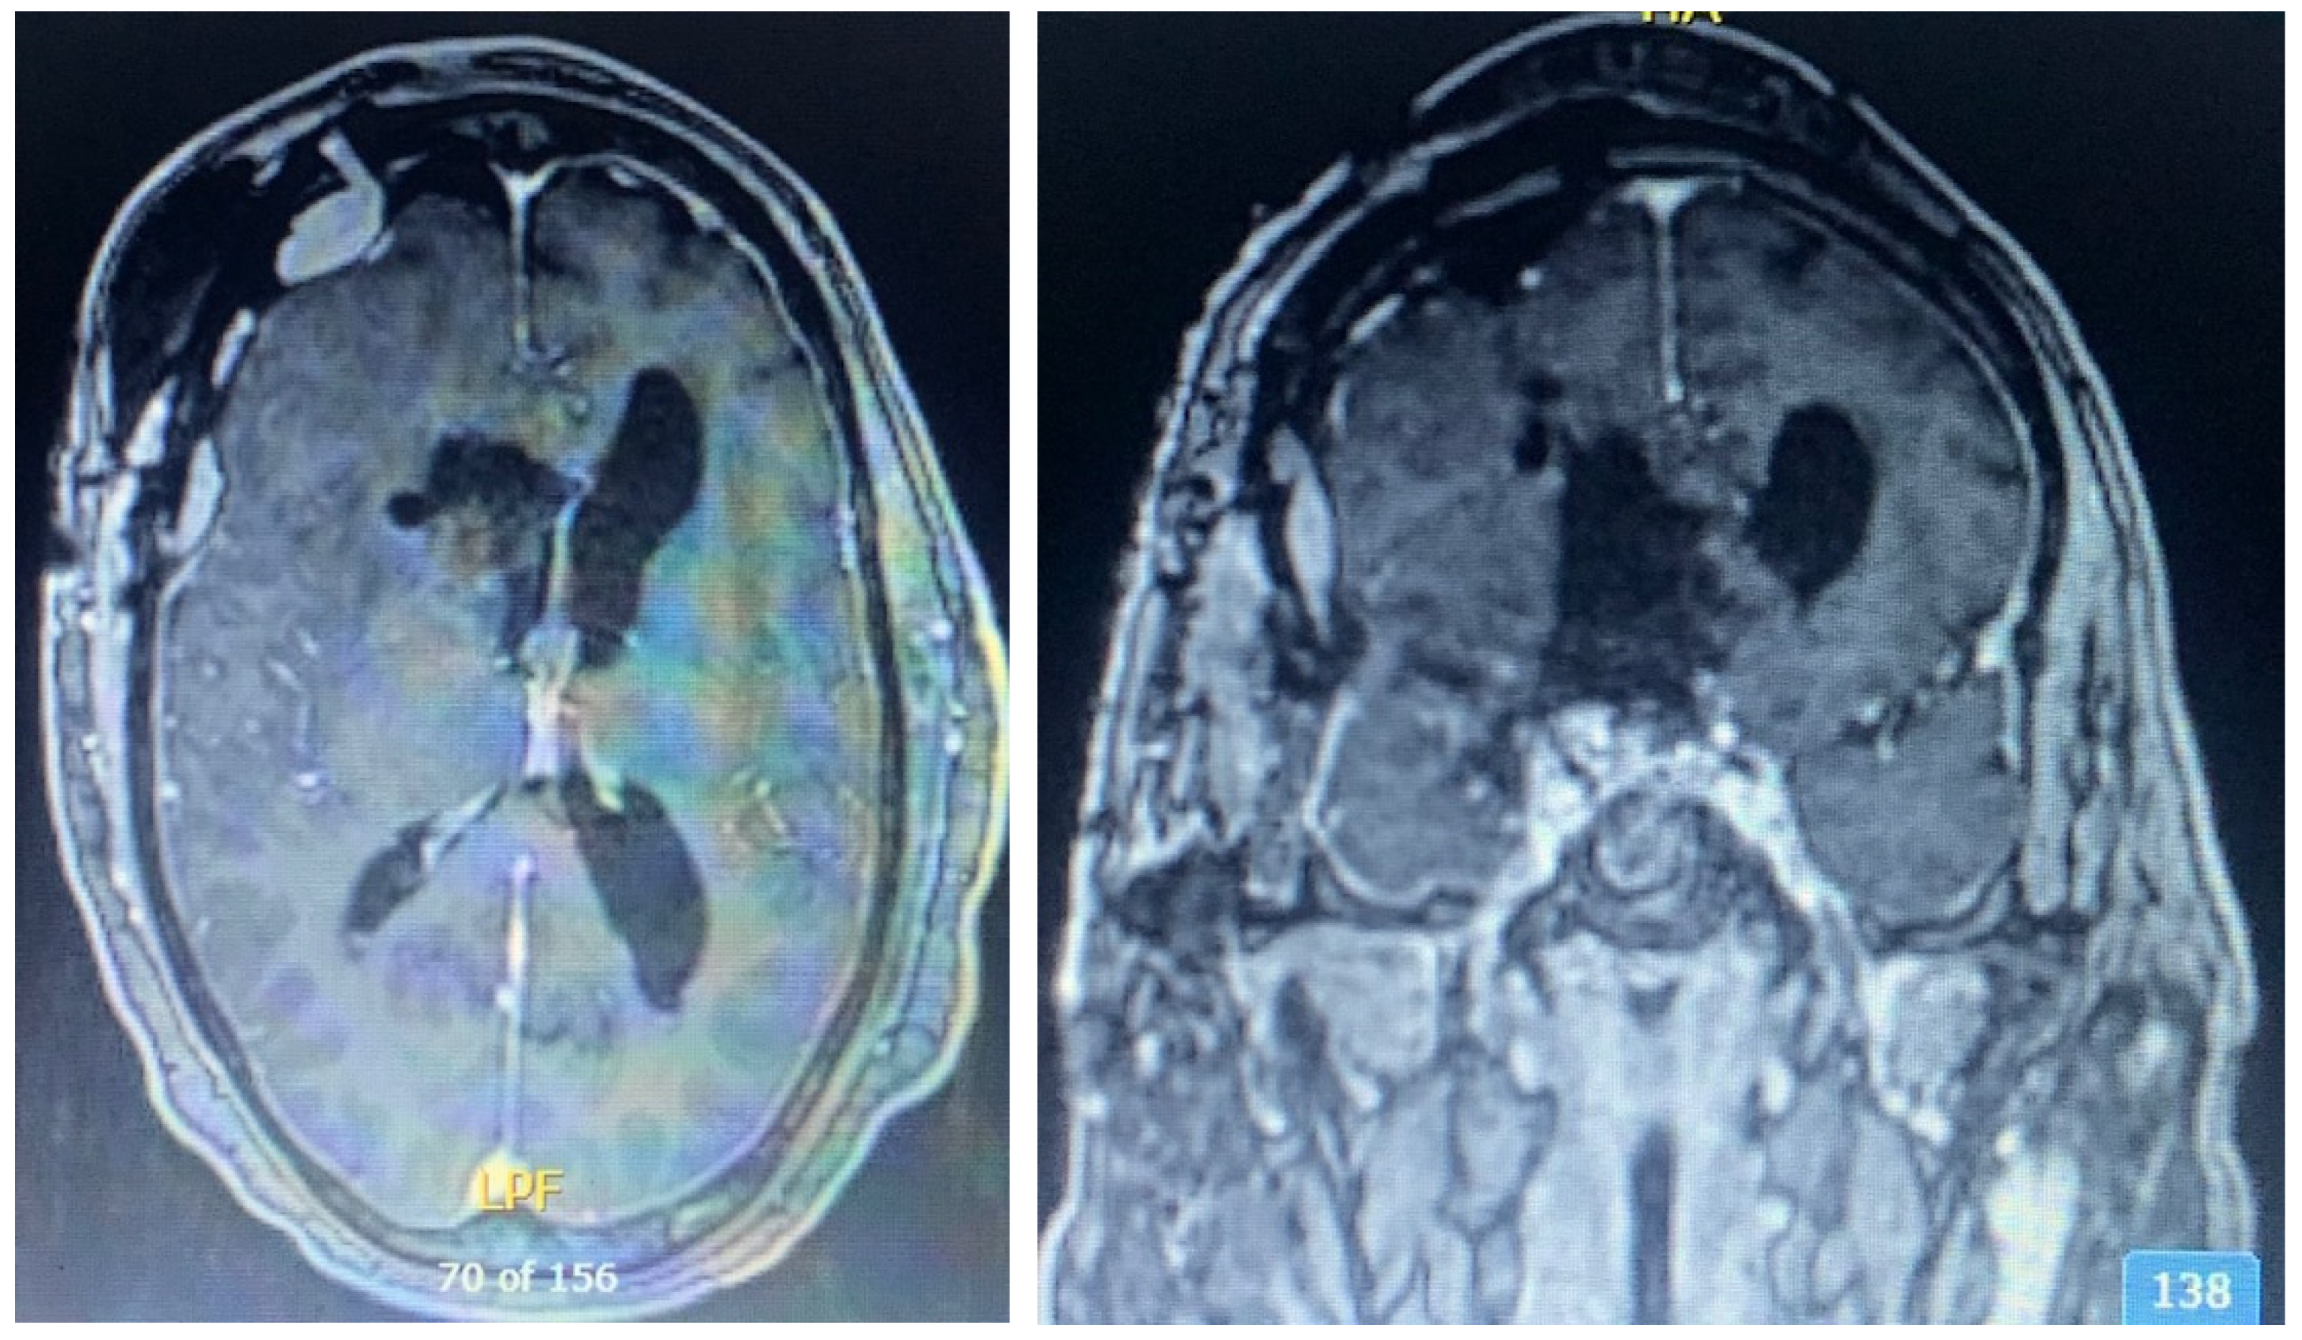

2.1. Case 1

2.2. Case 2